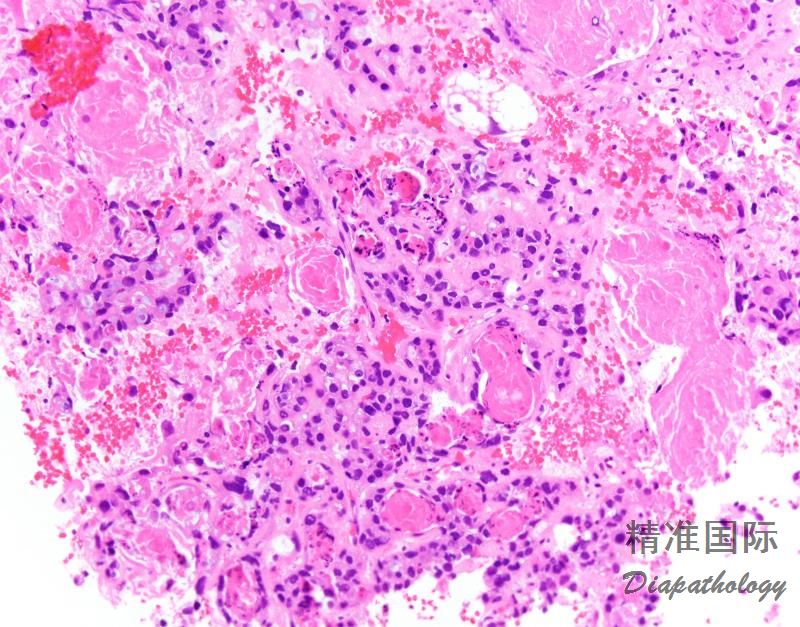

由胞浆透亮或嗜酸性,最少局部具有高级别核的多角形或鞋钉样细胞呈实性、乳头状或管状排列的肿瘤,属于 II 型子宫内膜癌。

肿瘤呈实性、乳头状、管状和囊状结构,各种结构比例变化很大,可以以一种结构为主;

实性结构常由大量透明细胞混杂嗜酸性细胞组成,而乳头状、管状和囊状结构主要由鞋钉样细胞组成(核大,突出于腺腔),其间散在透明和嗜酸性细胞;囊状结构常衬覆扁平细胞;

细胞异型性、多形性不一致,但最少有部分细胞为高级别核,表现为细胞核大,明显多形性,多数病例核分裂像多见,并可见病理性核分裂像;

近 2/3 病例可见 PAS 阳性且耐淀粉酶消化的细胞内和细胞间透明小体,类似于卵黄囊瘤中的透明小体;

肿瘤内乳头状区域可有砂粒体。